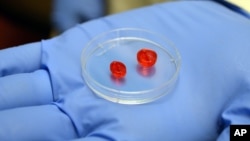

Human stem cells

The process is still slow, but Israeli 3-D printer manufacturer Nano Dimension, and Accellta, a company that produces IPS cells, now say they have tested a 3-D printer capable of fast production of human stem cells.